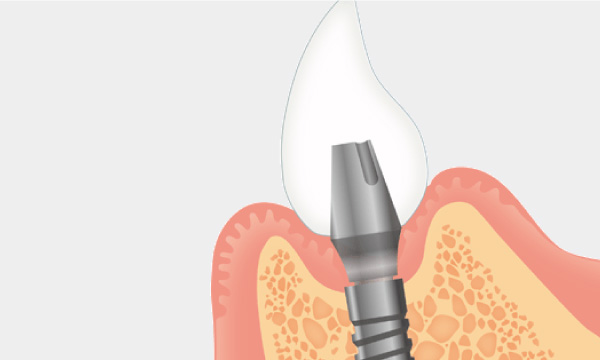

インプラント治療とは術前診査・診断を十分に行った上で、歯が抜けてしまった部分にインプラント(人工歯根)を埋め込み、その上から自然な見た目の人工歯を装着させるという治療法で、骨にしっかりとインプラント(人工歯)を定着させるため、自分の歯のようにしっかり、思い切り噛めるようになります。